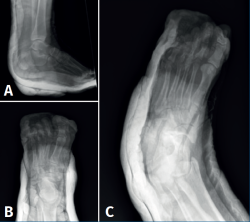

Figura 1. Radiografía anteroposterior (A) y lateral de tobillo (B). Radiografía anteroposterior (C) y oblicua (D) de pie con hallazgo de luxación periastragalina medial.

Se realizaron radiografías anteroposterior (AP) y lateral del tobillo, y AP y oblicua del pie, donde se diagnostica de luxación peritalar medial abierta (Figura 1).